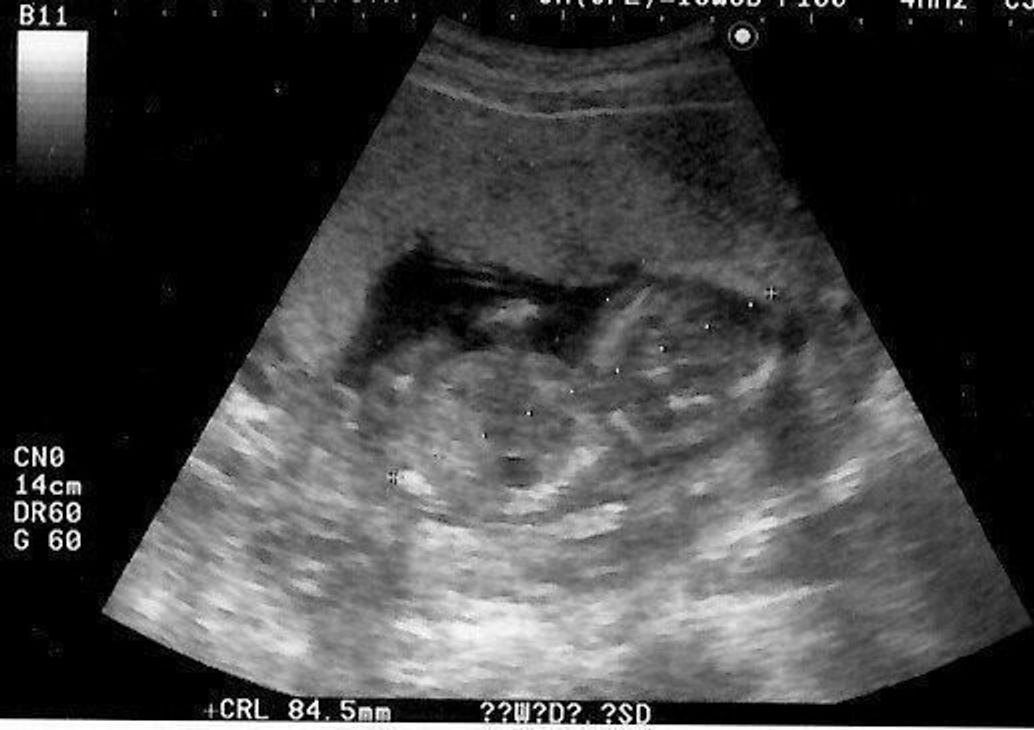

妊娠15週(15w)は妊娠4ヶ月です。 胎児の大きさは、身長が約11~16cm、体重が約40~1gほどになります。 胎盤の形成が完了し、赤ちゃんの身体や主要な器官もほぼ完成します。 身体が完成したことで、動きも活発になってきます。 自分の指を吸う「吸啜反射(きゅうてつはんしゃ)」がみられるかもしれません。 身体にはうっすら胎毛も生えてきますよ。 15週目に胎動を感 妊娠15週目は、妊娠4ヶ月の最終週で、胎盤がついに完成する時期です。 エコー検査の際、赤ちゃんの体勢によっては性別がわかることもあるでしょう。 この週で妊娠初期が終わります。 つわりなどで不安定だった体調が落ち着いてくる妊婦さんも多くなります。 今回は、コズレ会員のみなさんからお寄せいただいた妊娠15週目のエコー写真とその時のエピソードをご紹介します。 目次

中期妊娠中絶の方法と流れ ここでは、妊娠13週~満22週までの中絶手術について、受診から手術後までの一般的な流れや手術の方法等を解説します。 中期妊娠中絶の方法 中期妊娠中絶は、妊娠12週以降に行われます。子宮内の胎児がかなり大きくなって 妊娠15週の赤ちゃんの状態 妊娠15週目になると、赤ちゃんは羊水の中で活発に動くようになります。 超音波検査では、指しゃぶりをしている様子がよく見られるようになるでしょう。 ときには、超音波検査で性別がわかることもあります。 赤ちゃんの大きさ 15週目の終わりには、赤ちゃんは12センチくらいに、体重も50~70グラムくらいになります。 りんごくらいの大きさだという人